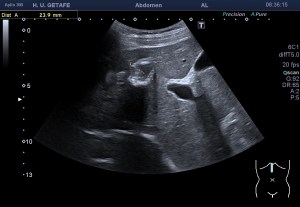

Al llegar al compartimento 6 me encuentro un tendón engrosado de tamaño y aspecto heterogéneo típico de afectación por tendinosis, con líquido en la vaina, te lo señala la imagen con flecha amarilla. Lo recorro y confirmo los hallazgos eje corto y eje largo, hago medidas y compruebo el doppler que marca Neovascularización asociada.

Observa las tres imágenes superiores, son muy ilustrativas, son comparativas de normalidad hallazgos patológicos, el izquierdo claramente patológico y el derecho claramente normal.